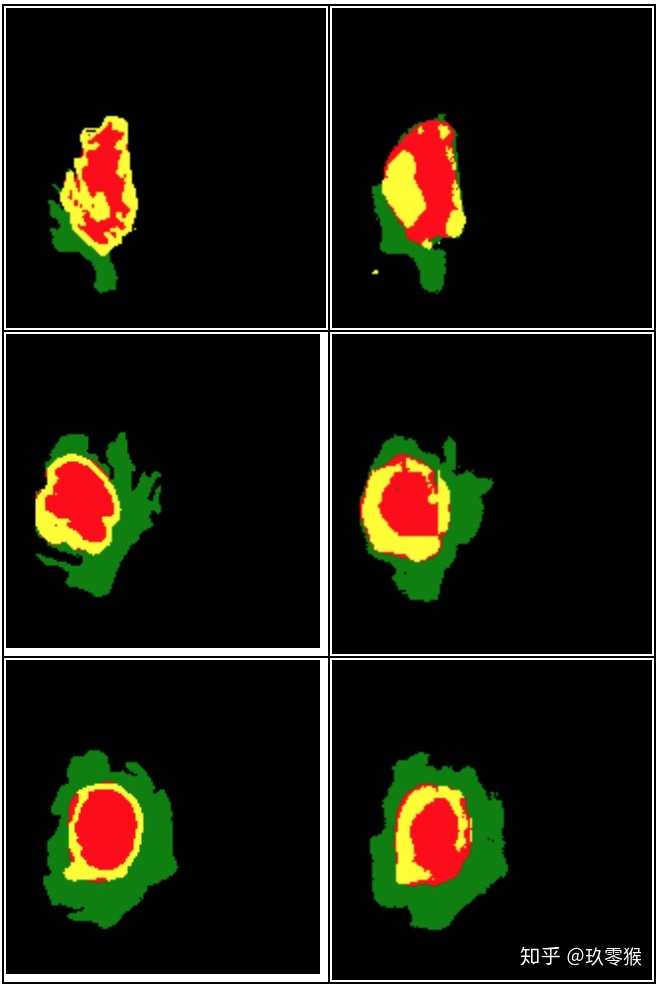

python .\test.py --name="Jiu0Monkey_FCN8s_woDS" --mode="GetPicture"

运行下面指令评价测试结果以及GT文件的指标,想了解更多指标的信息包括Dice、Hausdorff、IOU、PPV等,可以参考我这一篇(分割常用评价指标)

运行的结果: